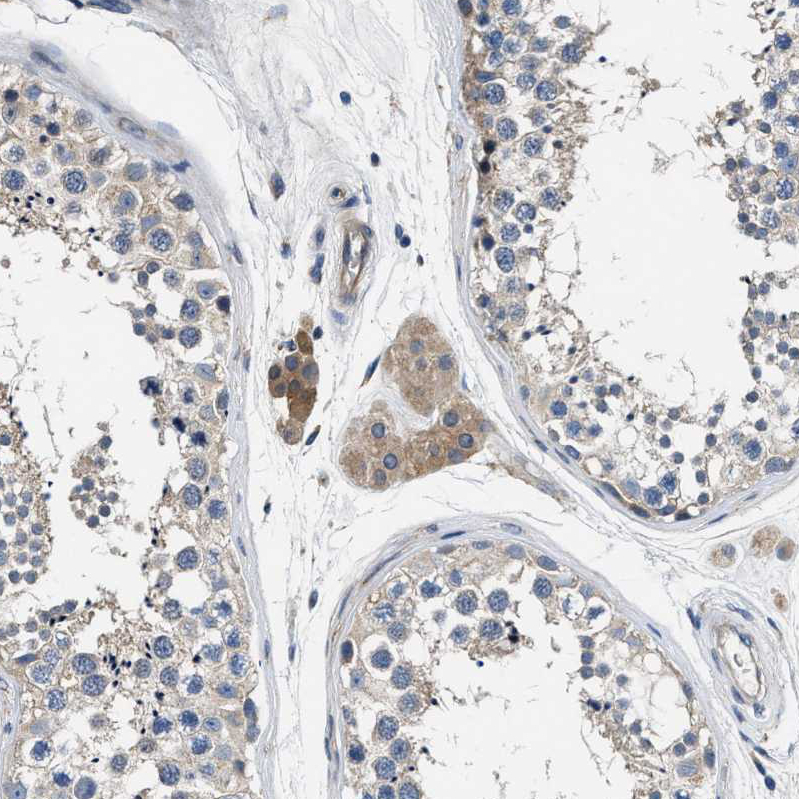

Immunohistochemistry analysis in human placenta and testis tissues using HPA021019 antibody. Corresponding TGM2 RNA-seq data are presented for the same tissues.